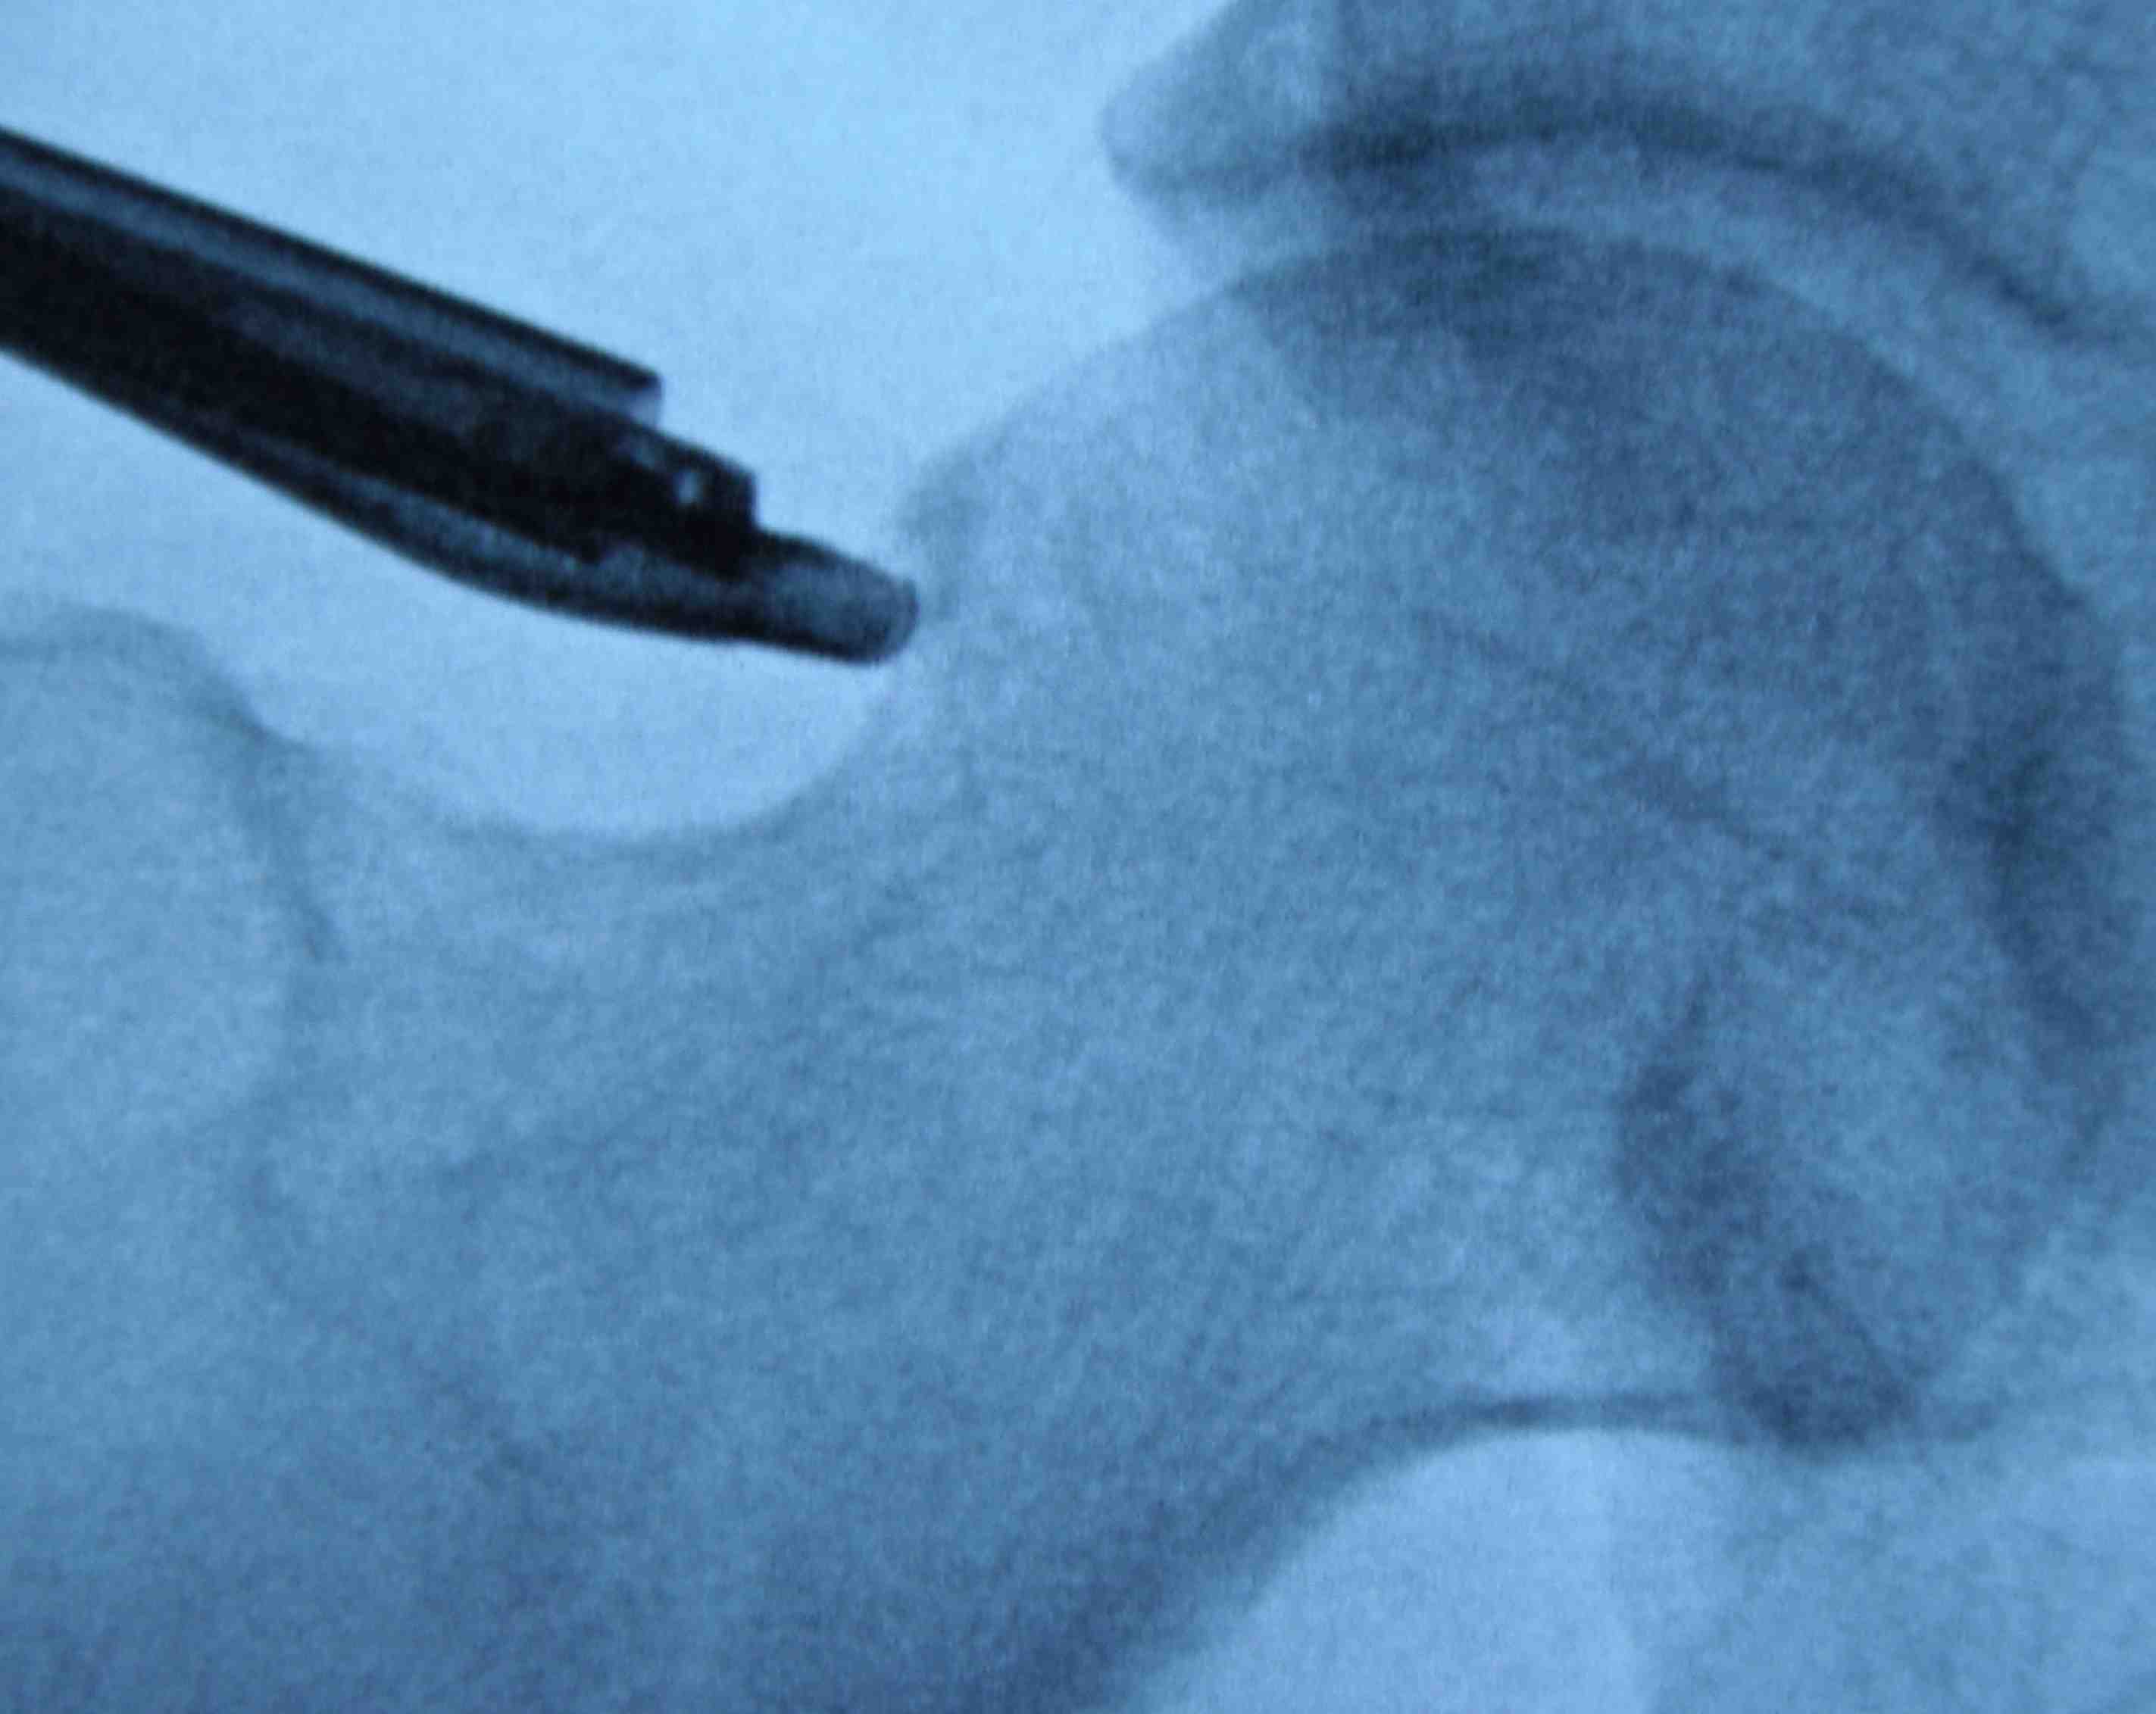

Mid anterior portal